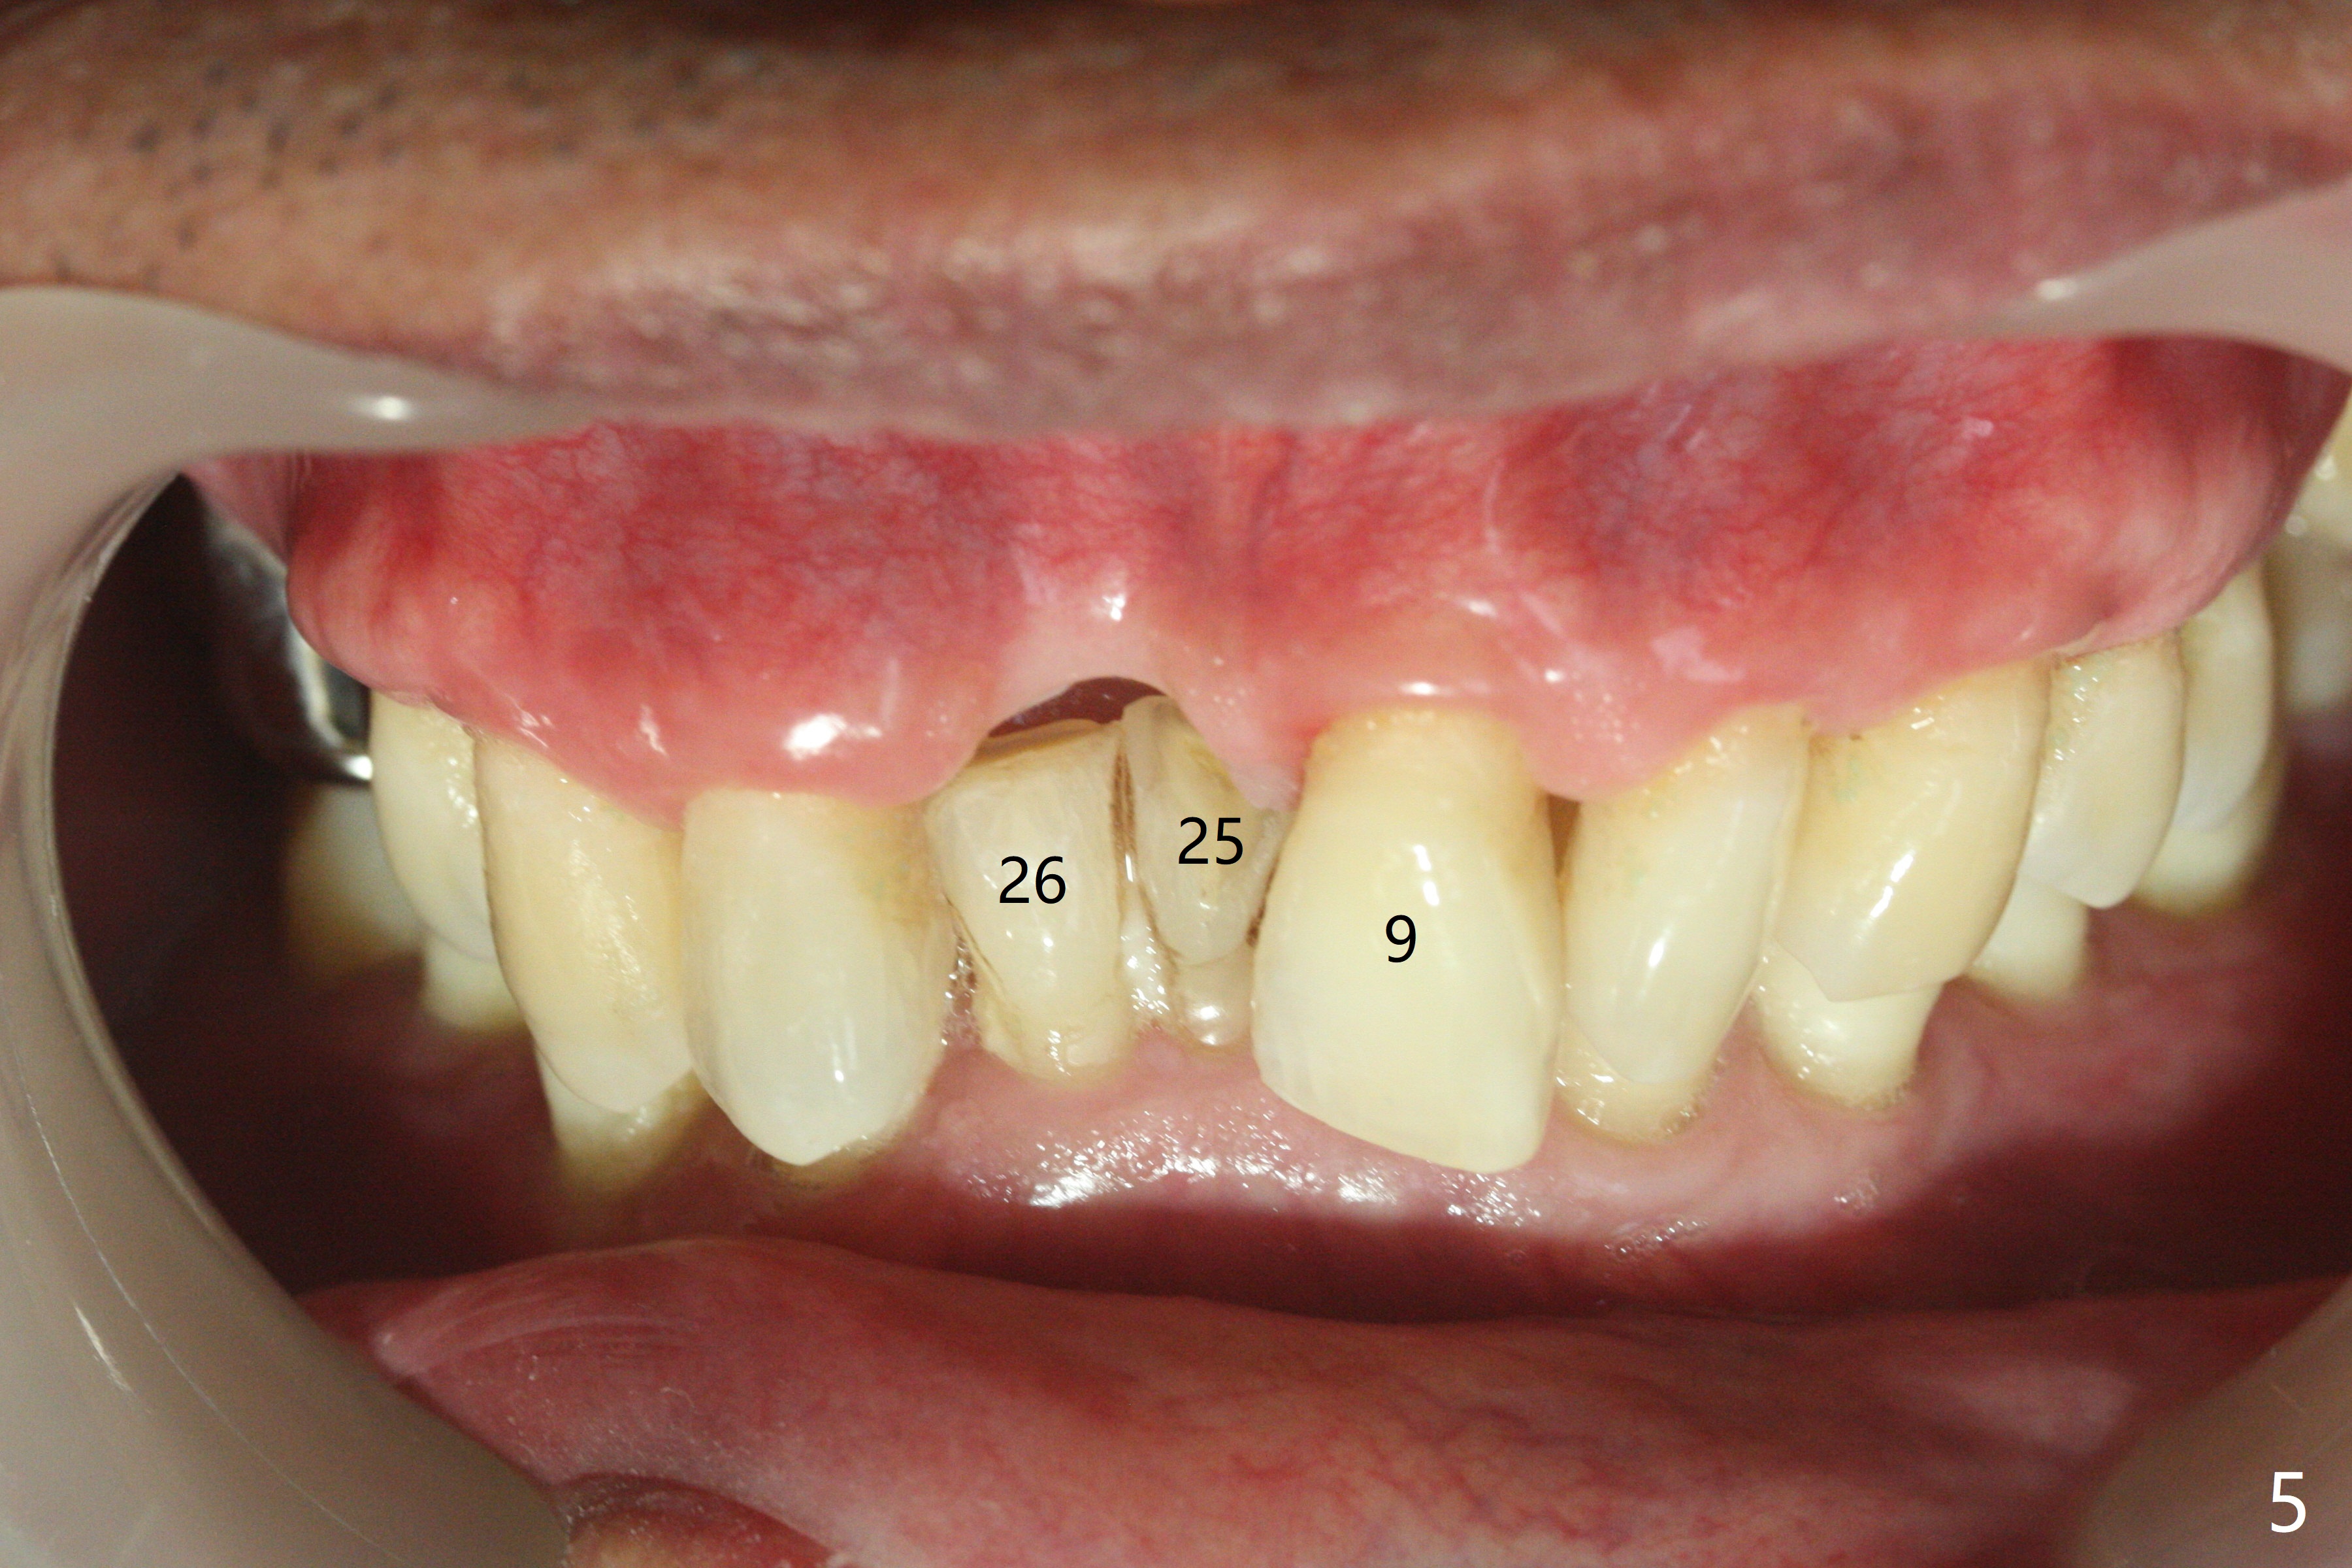

A 69-year-old man (ex-soldier) had the tooth #8 extracted for a flipper nearly 8 years earlier (Fig.1 (obliterated canal)). A denture tooth is added at #14 after extraction in NY a few years later (Fig.2). In spite of sufficient bone width at #8, a 2.5x10 mm mini implant will be chosen to reduce the chance of palatal thread exposure (Fig.3 P). A 5x8.5 mm implant will be placed at #14 to achieve enough stability and not cause sinus complication (Fig.4). Take preop photos to show the anterior deep overbite and overjet. In fact the patient canceled the surgery. Two years later, he returns with history of right TMJ dislocation, which may be related to reduced mastication efficiency and partial edentulism (Fig.5,6).